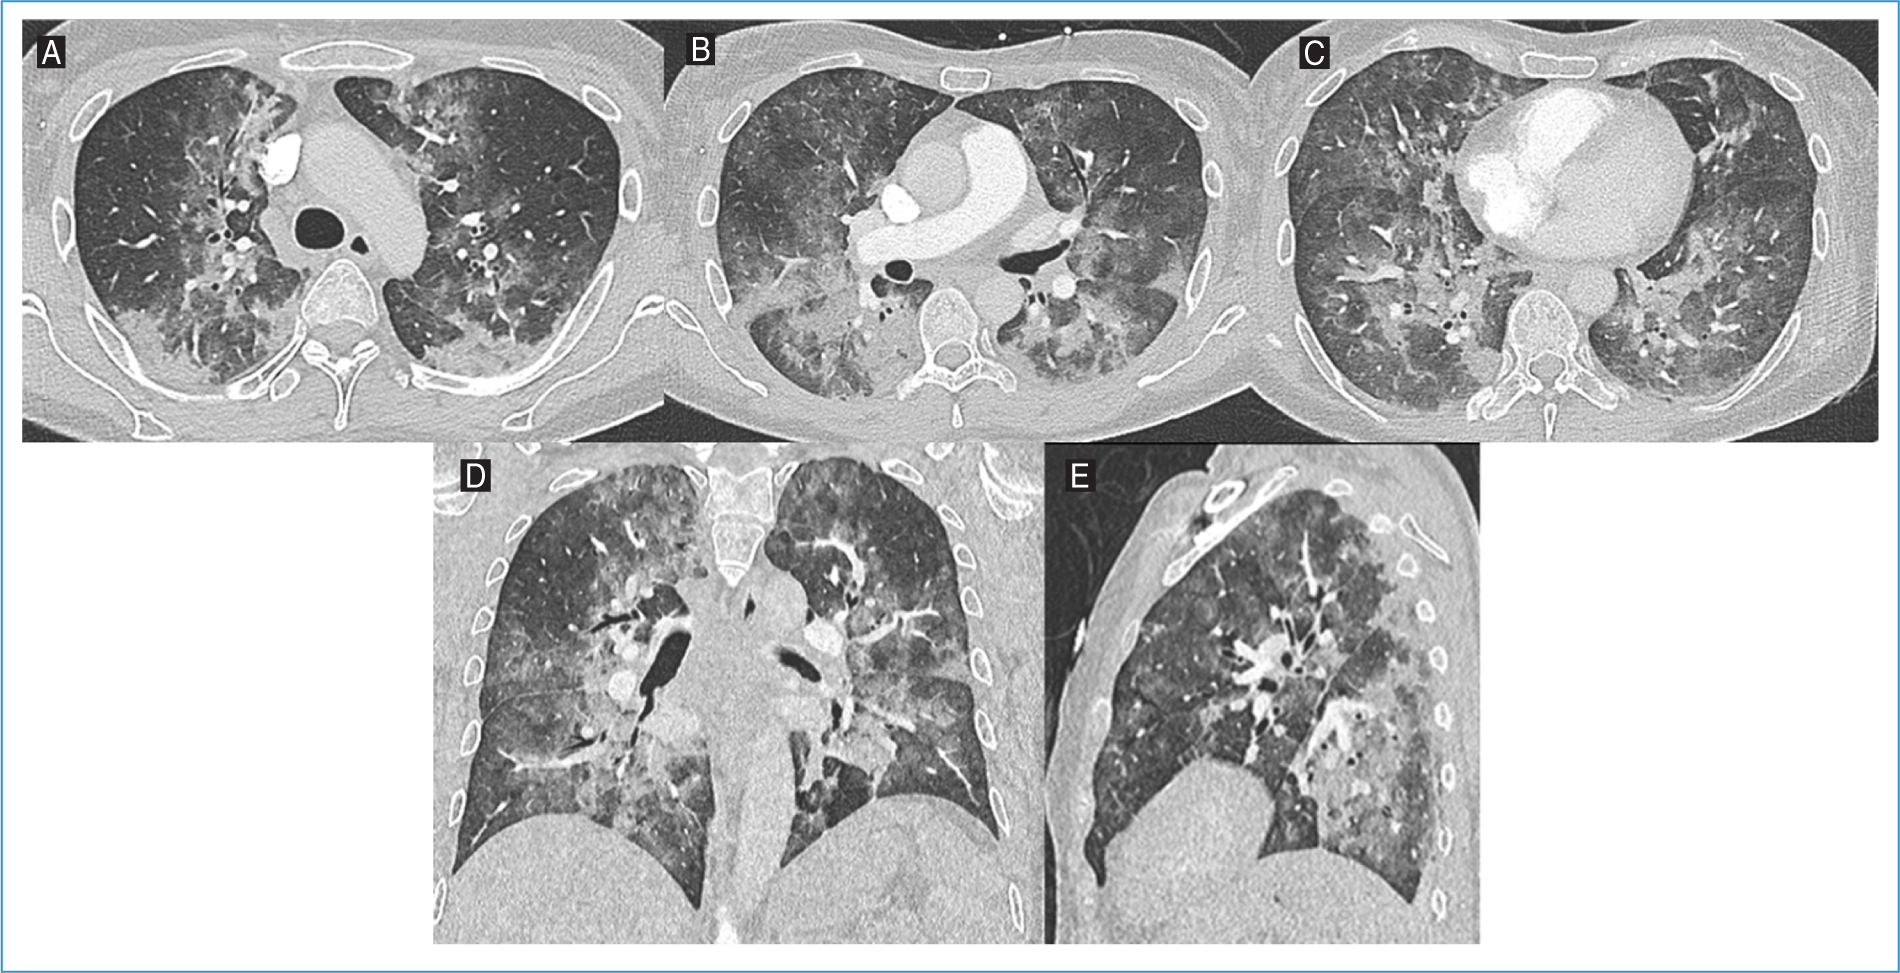

Thoracic CT angiography ruled out pulmonary embolism and showed diffuse ground-glass opacities, predominantly in the upper and middle lung lobes, plus reticular opacities and septal thickening, suggestive of an inflammatory/infectious process (Fig. 3). The patient was admitted for further investigation and management. Initial treatment consisted of amoxicillin-clavulanate, azithromycin, and corticosteroids. However, due to rapid respiratory deterioration, the antibiotic regimen was changed to piperacillin-tazobactam within 48 h. Bronchoscopy revealed thick mucus secretions bilaterally, and BAL diagnosed PJP. Empirical antibiotics were de-escalated, and targeted treatment with high-dose TMP-SMZ and corticosteroids was initiated. Additional diagnostic tests, including bacterial cultures, respiratory viral panels, and galactomannan antigen, were negative. Cytological analysis of BAL showed no malignant cells.

Figure 3. Axial lung window images of the A: upper, B: middle, and C: lower lobes, along with D: coronal and E: sagittal reconstructions from thoracic computed tomography angiography of Patient #3. Diffuse ground-glass opacities, predominantly in the upper and middle lung lobes, are present, accompanied by reticular opacities and septal thickening, suggestive of an inflammatory/infectious process.